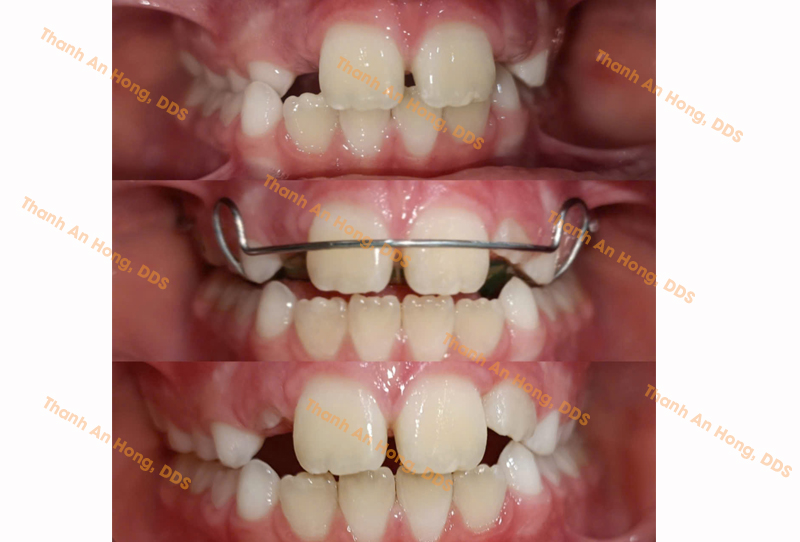

Chỉnh cắn ngược

Chỉnh mắc cài giảm hô

Chỉnh móm/cắn ngược với mắc cài